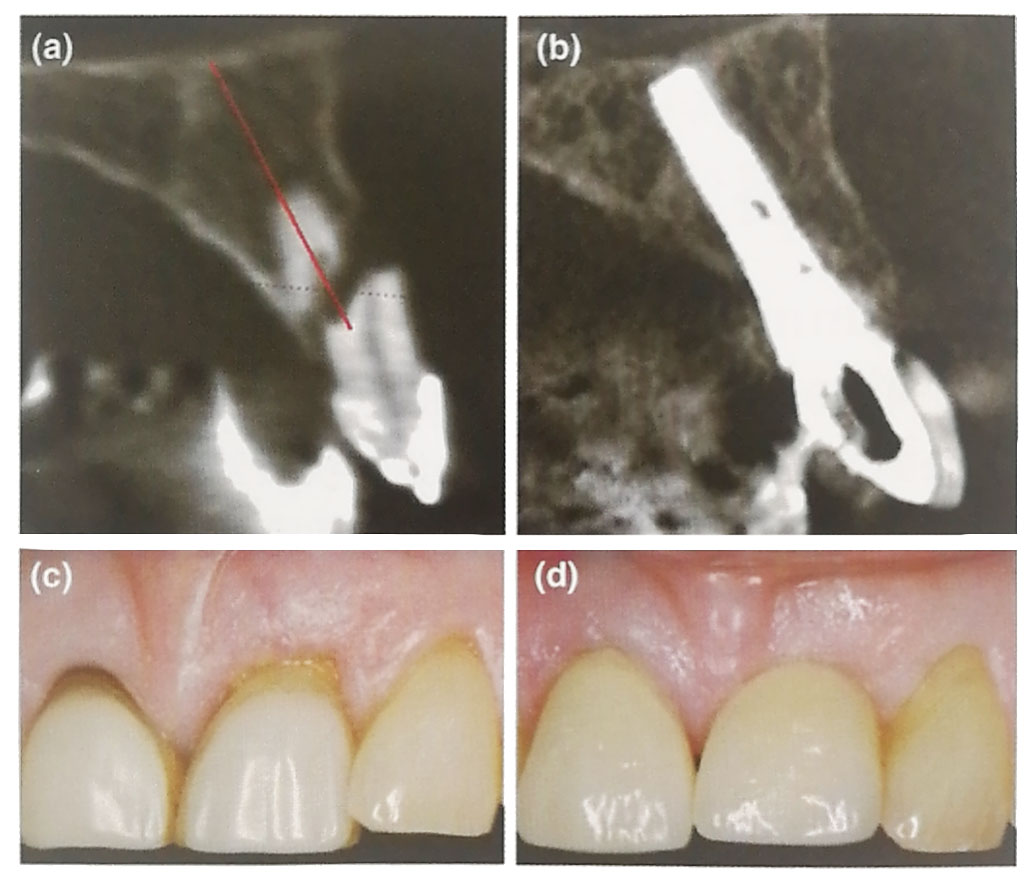

(a)术前检查CBCT显示唇侧骨严重缺损和水平向根折。

(b)5年随访时CBCT显示唇侧骨重建达到种植体肩台水平。

(c)术前照片显示左上中切牙水平向根折后软组织水肿伴轻微退缩(PES11)

(d)即刻种植、即刻修复、不翻衅植骨后5年随访照片显示种植体周围唇侧软组织量增加且稳定。